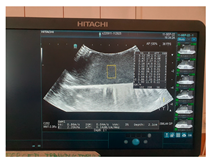

| Ultrasound |  |  |  |

| Ultrasound |  |  |  |

| Ultrasound |  |  |  |

| Ultrasound |  |  |  |

| Ultrasound |  |  |  |

| Ultrasound |  |  |  |